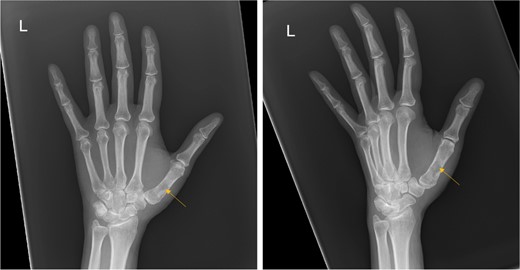

X-ray showed a well-defined non-aggressive lytic bony lesion of the first metacarpal bone (Fig. 1). Magnetic resonance imaging (MRI) showed a grossly stable skin and subcutaneous multilobulated soft tissue mass located at the palmar aspect of the wrist joint measuring 6 × 2 × 3.3 cm3 in its maximum anteroposterior, transverse and craniocaudal dimensions, respectively (Figs 2 and 3). The lesion showed low and high signals in T1 - and T2-weighted images with homogenous contrast enhancement. The lesion was inseparable from the flexor carpi radialis and palmaris longus tendons without definite invasion or encasement. The lesion was not in continuity, however, with the serpiginous lytic bony lesion noted at the first metacarpal bone exhibiting low T1 and high T2 signals with peripheral enhancement and no cortical destruction or associated soft tissue component (Fig. 4).

Frontal and oblique radiograph of the left hand showing a non-aggressive lytic lesion of the left 1st metacarpal bone with internal sclerosis.